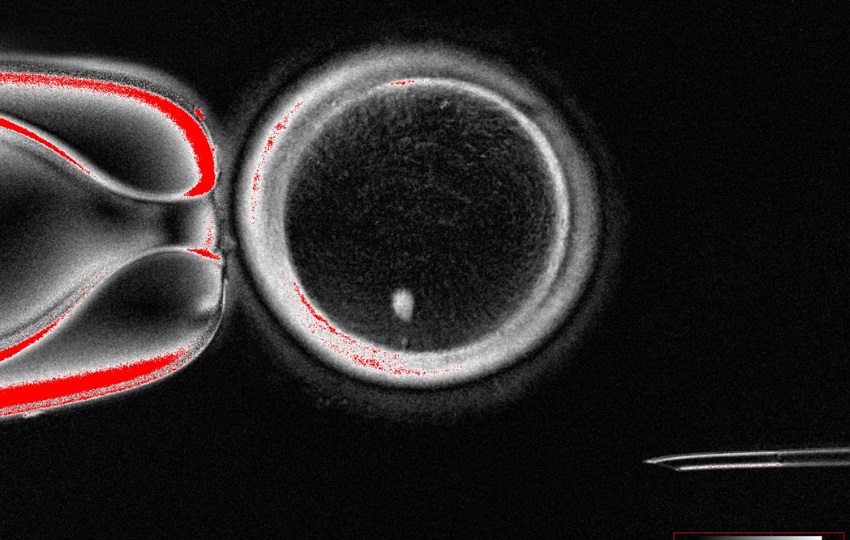

Ovocito humano con transferencia nuclear de células somáticas con huso visible (punto brillante en el interior) antes de la fecundación. Foto: EFE

Una posible alternativa podría ser la transferencia nuclear de células somáticas, un proceso mediante el cual se trasplanta el núcleo de una de las células somáticas del propio paciente (como las células de la piel) a un óvulo donante al que se le ha extraído el núcleo, lo que permite que la célula se diferencie en un ovocito funcional.

Sin embargo, mientras que los gametos estándar tienen la mitad del número habitual de cromosomas (un conjunto de 23), las células generadas a partir de la transferencia nuclear de células somáticas contienen dos conjuntos de cromosomas humanos (46), lo que provocaría que los cigotos resultantes tuvieran un conjunto extra de cromosomas, explica Nature.

El equipo extrajo el núcleo de las células somáticas de la piel y lo insertó en ovocitos de donantes a los que se les había extraído el núcleo.

Para resolver el problema del conjunto extra de cromosomas indujeron un proceso que denominaron "mitomeiosis", que imita la división celular natural y provoca que se descarte un conjunto de cromosomas, dejando un gameto funcional.